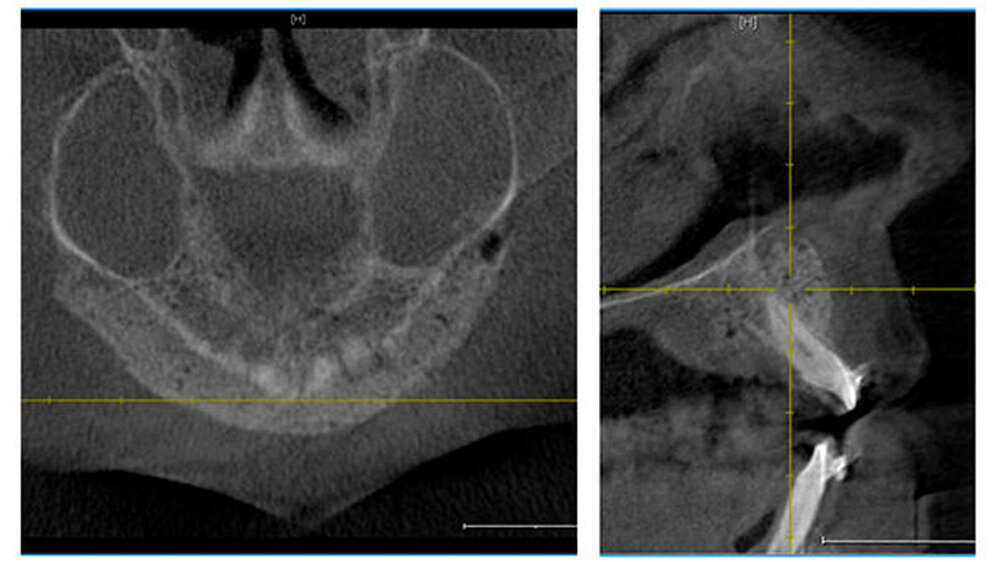

Eine 20-jährige Patientin stellte sich erstmalig zur Implantat- und Distraktionsberatung in unserer Abteilung für Mund-, Kiefer- und Gesichtschirurgie vor. Diagnostisch lagen eine mandibuläre Retrognathie, retinierte und verlagerte Zähne 18, 28, 38 und 48, ein Zapfenzahn 12, ein fehlender Zahn in regio 022, eine Mittellinienverschiebung und ein Engstand der Oberkieferfront vor (Abbildungen 1a bis d). Im Rahmen der klinischen Untersuchung und basierend auf dem Auswertungsergebnis der Digitalen Volumentomografie (DVT) führten wir bei der Patientin im Hinblick möglicher therapeutischer Maßnahmen eine differenzial-therapeutische Beratung durch.

Klinisch als auch radiologisch lag eine konvergierende Wurzelstellung der Zähne 21 und 23 vor. Eine unkomplizierte implantatprothetische Versorgung der Lücke 022, das heißt ohne Verletzung der benachbarten angulierten Zähne, erschien nicht möglich. Die Schwierigkeit bestand darin, die Lücke 022 durch körperliche Bewegung der Zähne zu öffnen, was sich bislang mittels festsitzender Apparatur als frustran erwiesen hatte. Der Patientin wurde aufgrund der vorliegenden Diagnose eine parodontal akzelerierte osteogenetische Orthodontie (PAOO) im Bereich des linken Oberkiefers empfohlen.